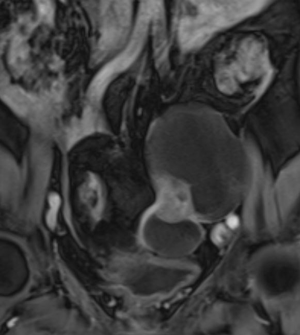

МР-диагностика рака яичников